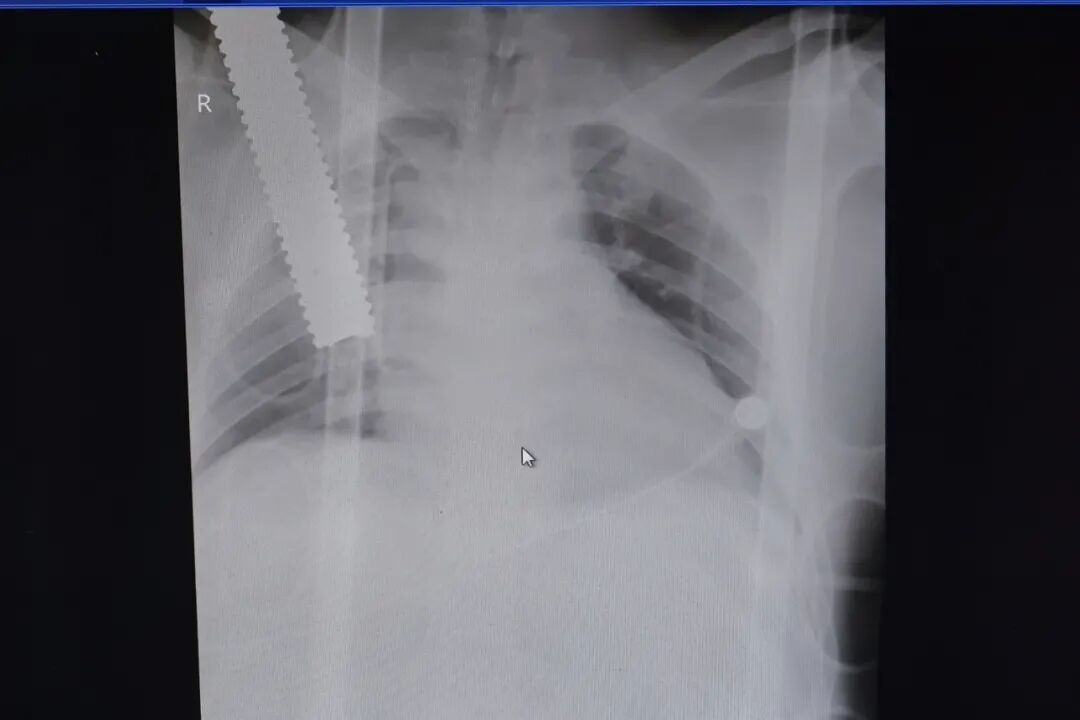

当天,吴先生被送到区中心医院急救时,右侧锁骨处插着一根直径约3厘米的螺纹铁棒,本人已出现了休克症状,情况十分危急。

(下图可能会产生不适,请谨慎点击查看)

区中心医院立即开通绿色通道,启动抢救应急预案,多学科汇同实施手术抢救,仁济医院心血管外科主任医师黄日太也第一时间来到现场实施联合救治。经过3小时的手术,铁棒被从吴先生的体内安全取出,破损的心脏以及肺部也得到及时妥善的缝合。

参与整个抢救过程的区中心医院胸外科主治医师徐超介绍,当时铁棒扎入吴先生右侧胸腔深度超过20厘米,右肺上叶已被贯穿,心包张力极高,心脏严重压塞。如果不及时手术,急性心包填塞会造成血液循环的持续障碍,患者很快就会有生命危险。“多亏医联体专家及时联合施救,吴先生才能转危为安。”